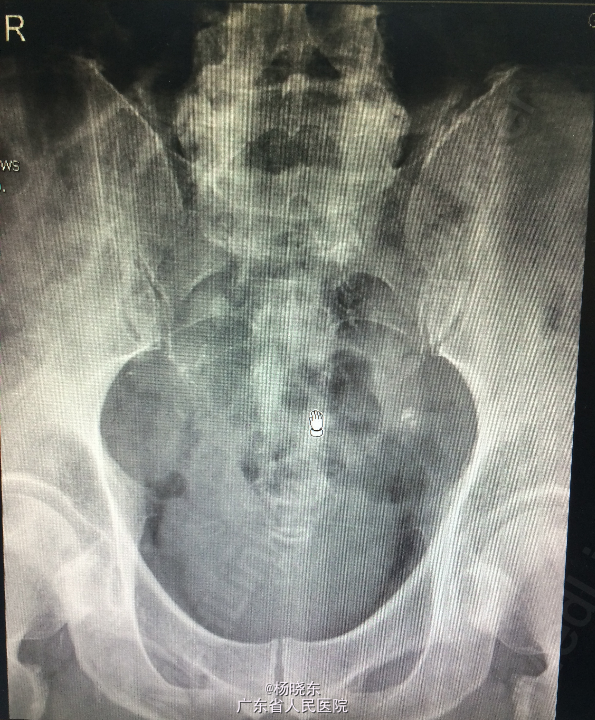

查体:贫血貌,心肺腹查体无特殊。 辅查: 1.全长双下肢长骨正位+尾椎正侧位+肋骨正位+右关节正位+骨盆正位+腰椎正侧位+下胸椎正侧位放射常规照片示:考虑多发性骨髓瘤(多发骨病变)。1、颈椎退行性变 2、腰椎退行性变;多个椎间盘病变;L1椎体轻度压缩性骨折。3、胸椎退行性变。 2.骨髓活检:可见少许造血成分,粒红比例大致正常,均以中晚幼阶段细胞为主,全片可见三个巨核细胞,形态未见明显异常。并可见浆细胞散在。 3.骨髓-外周血涂片:MM-骨髓增生活跃,浆细胞占58.0%,其中原幼浆占53.5%,外周血占2.0%。